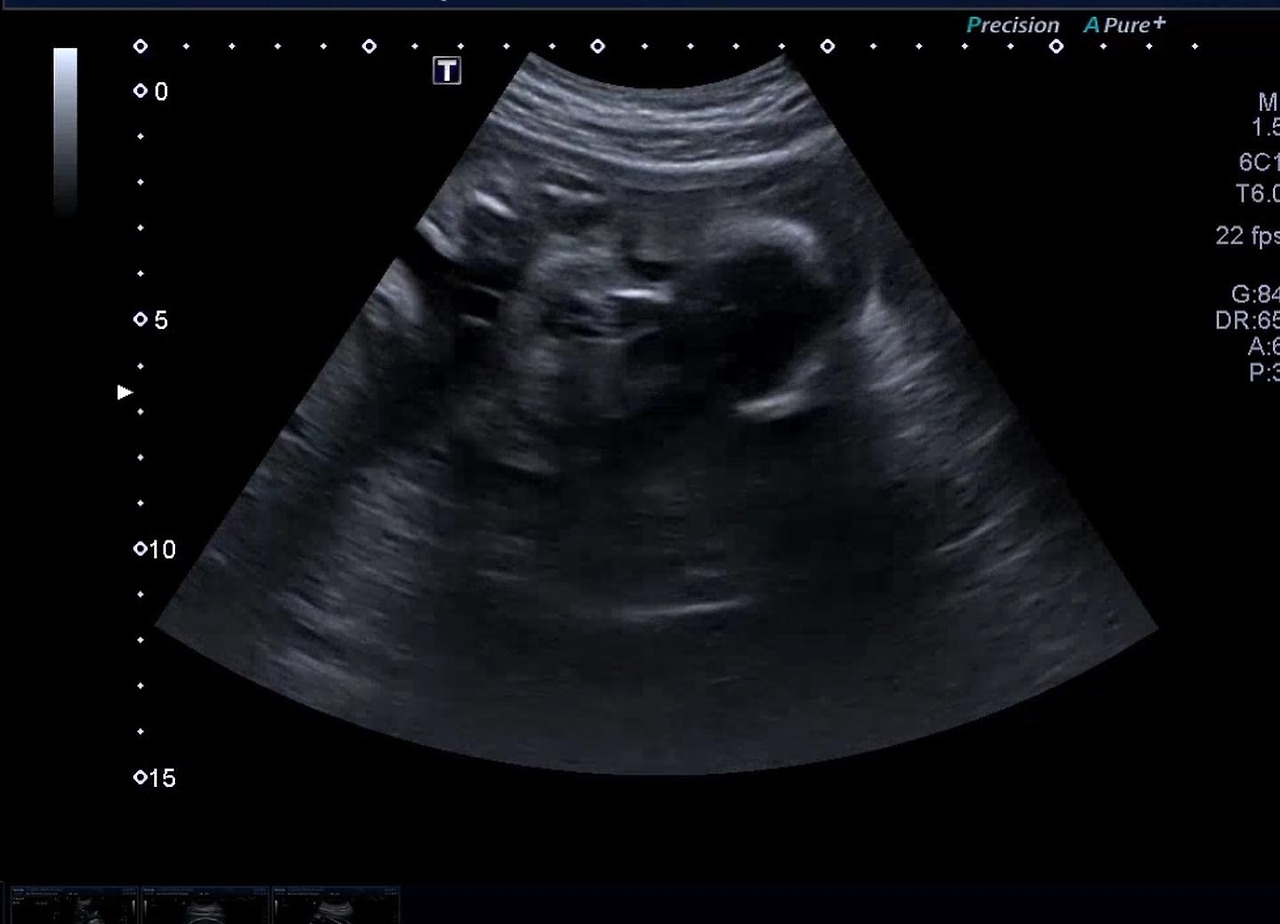

다올이 머리카락

29주 머리카락.jpg

귀여운 다올이 머리카락이라니..! 선생님께서 벌써 다올이 머리숱 부자라고 말씀해주셨다.

아빠도 엄마도 머리숱이 많았어서 그런가 보다 신기신기